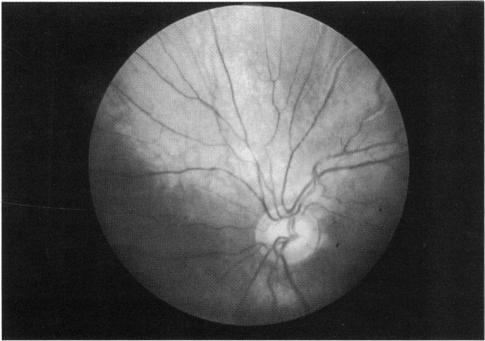

We identified five patients with the organoid nevus syndrome. Four had a classic sebaceous nevus in the facial and scalp area, and 2 had seizures and arachnoid cysts. All 5 patients had an epibulbar tumor, which proved to be a complex choristoma in one case that was studied histopathologically. A characteristic ophthalmoscopic feature, observed in the 4 patients with clear ocular media, was a flat yellow discoloration of the posterior fundus, of variable size and shape, which appeared to correlate with a dense plaque noted on ultrasonography and computed tomography. In 1 case, histopathologic examination showed that this posterior lesion contained intrascleral cartilage.

Our observations and a review of the literature indicated that the organoid nevus syndrome has varied manifestations. Like the closely related phakomatoses, it often occurs as a forme fruste, without full expression of the syndrome. The most important ocular manifestations are an epibulbar mass, compatible with a complex choristoma, and focal yellow discoloration in the fundus, probably related to intrascleral cartilage.

我们确定了5例器官样痣综合征患者。4例在面部和头皮区域有典型的皮脂腺痣,2例有癫痫发作和蛛网膜囊肿。所有5例患者均有眼球表面肿瘤,其中1例经组织病理学研究证实为复合性脉络膜瘤。在4例眼介质清晰的患者中观察到一个特征性的眼底镜特征,即眼底后部有扁平的黄色变色,大小和形状各异,这似乎与超声检查和计算机断层扫描中发现的致密斑块相关。在1例中,组织病理学检查显示该后部病变含有巩膜内软骨。

我们的观察和文献回顾表明,器官样痣综合征有多种表现。与密切相关的错构瘤一样,它常以不完全型出现,综合征未完全表现出来。最重要的眼部表现是与复合性脉络膜瘤相符的眼球表面肿块,以及眼底的局灶性黄色变色,可能与巩膜内软骨有关。